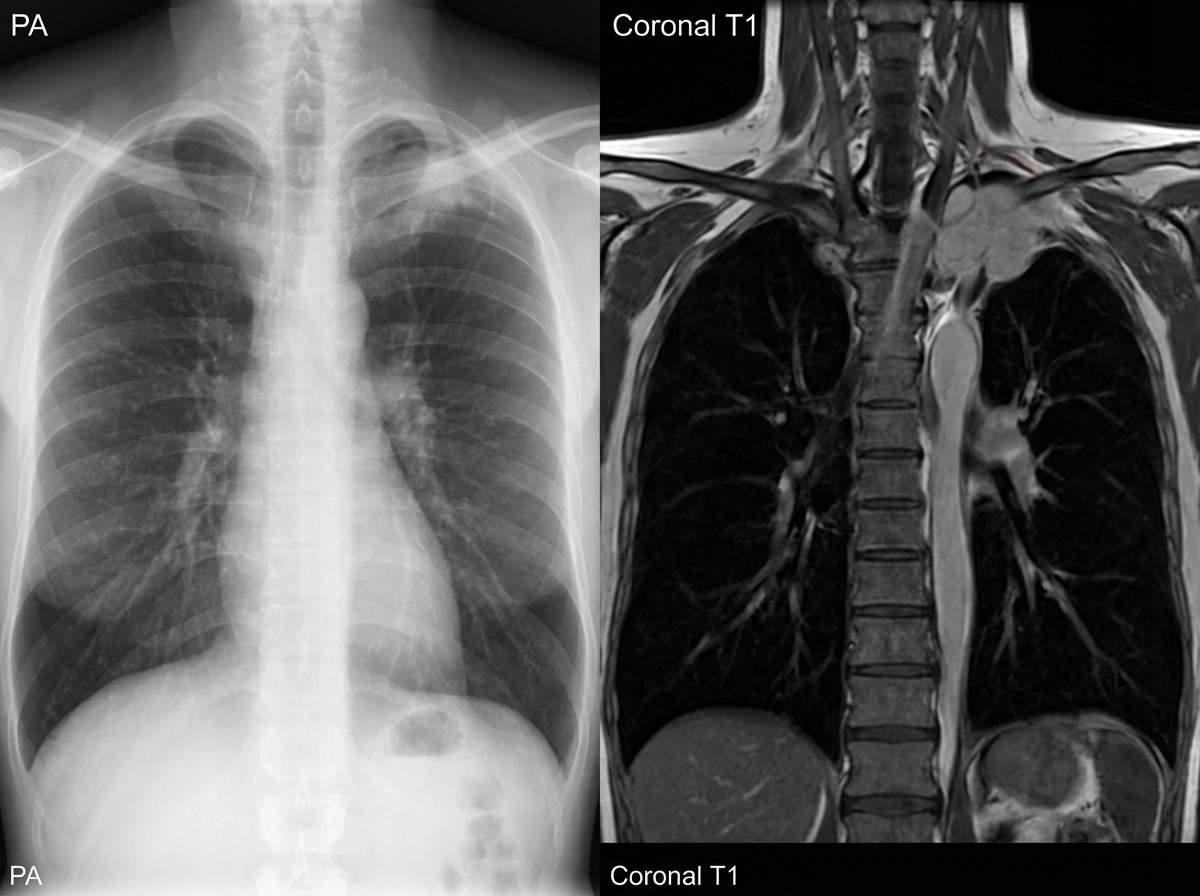

A 16-year-old girl presents with episodes of sharp pain in her left upper limb. She says her symptoms gradually onset a few months ago and have progressively worsened. She describes her pain as severe and feeling like “someone stabbing me in my arm and then the pain moves down to my hand”. She says the pain is worse after physical activity and improves with rest. She also says she has some vision problems in her left eye. The patient is afebrile, and her vital signs are within normal limits. On physical examination, there are no visible deformities in the shoulders or upper extremities. Palpation of her left upper limb reveals tenderness mainly near her neck. Mild left-sided ptosis is present. There is anisocoria of her left pupil which measures 1 mm smaller than the right. The right upper limb is normal. A plain radiograph and an MRI are ordered (shown in the image). Which of the following focal neurologic deficits would most likely be seen on the left hand of this patient?